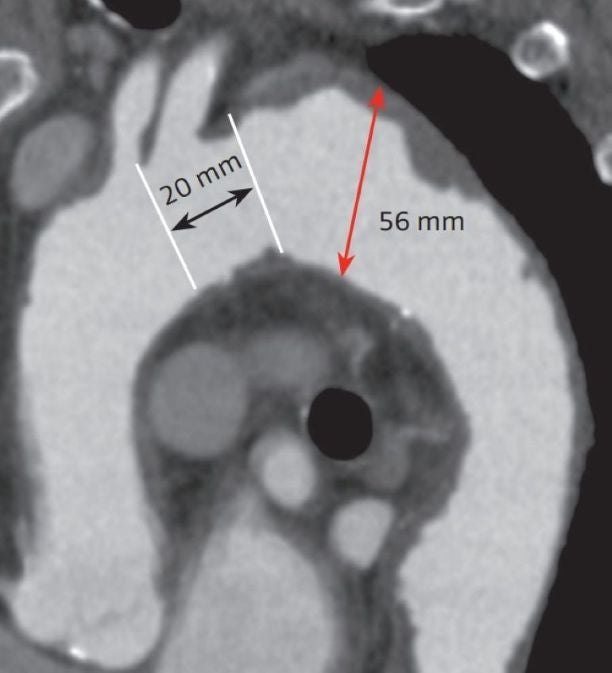

症例は 78歳、男性。拡大傾向のある遠位弓部大動脈瘤(紡錘状動脈瘤、最大径56 mm)を認めている。大動脈弓部から腹部大動脈に至るまでの胸部大動脈全域に毛羽立ちながら突出している壁在血栓を認めるshaggy aorta症例であった。

左総頸動脈起始部から動脈瘤までの距離が20.1 mmであり、Zone 2 TEVARでの治療方針となった(図2)。